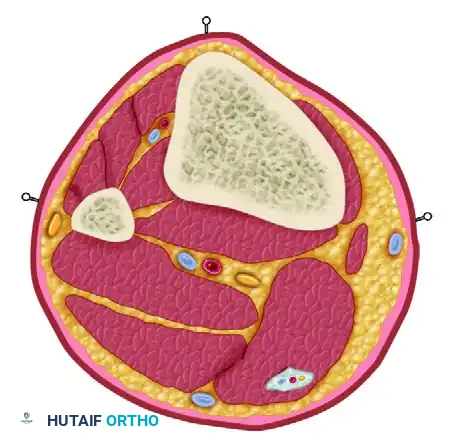

Cross-Sectional Anatomy and Safe Zones

The most critical technical aspect of external fixation is the safe insertion of pins. The surgeon must possess an intimate knowledge of cross-sectional anatomy to avoid neurovascular impalement and muscle tethering.

Surgical Warning: Pins inserted through muscle bellies or tendons will tether the muscle, restricting its excursion. This leads to severe pain, joint contractures, and potential tendon rupture. Always insert pins through intermuscular planes or directly into subcutaneous bone borders where possible.

The Tibia

The tibia is the most common site for external fixation. The anteromedial face of the tibia is subcutaneous and represents the optimal "safe corridor" for pin insertion along its entire length.

* Proximal Tibia: Pins can be placed from medial to lateral or anterior to posterior. Avoid the common peroneal nerve laterally at the fibular neck.

* Middle and Distal Tibia: The anterior tibial artery and deep peroneal nerve lie closely applied to the interosseous membrane and the lateral cortex of the tibia. Pins must be placed strictly on the anteromedial surface.